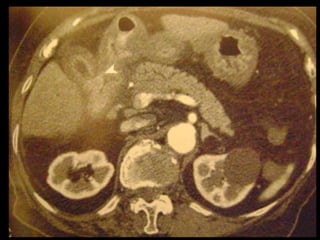

Achados na TC: cálculos biliares, espessamento da

parede, alterações inflamatórias

perivesiculares, bile com alta

atenuação, borramento da interface VB-fígado e

aumento transitório da atenuação do fígado

perivesicular;

Colecistite aguda US é a modalidade de imagem de escolha; Em geral, a TC é realizada para avaliar pacientes com suspeita de complicações do quadro de colecistite aguda, como perfuração por exemplo. Achados na TC: cálculos biliares, espessamento da parede, alterações inflamatórias perivesiculares, bile com alta atenuação, borramento da interface VB-fígado e aumento transitório da atenuação do fígado perivesicular;